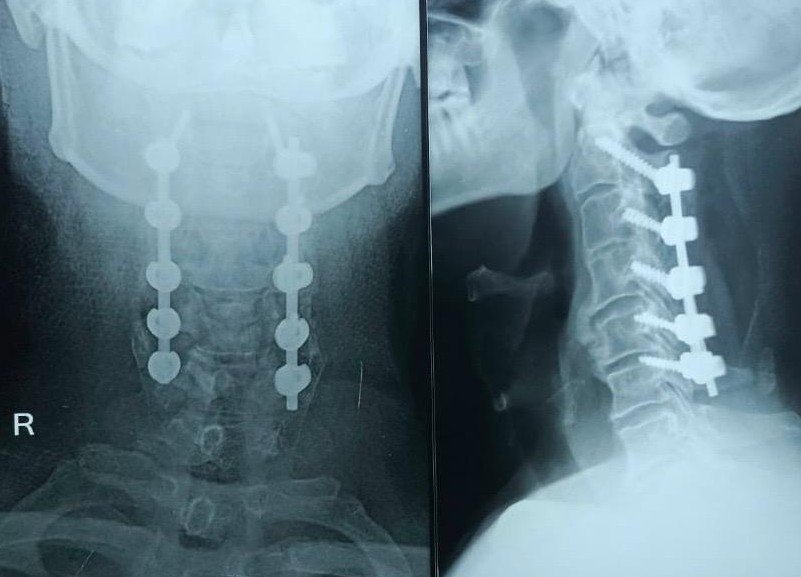

In cases like this, every minute matters — but even after a week, decompression can still make a difference. We planned an urgent: C2–C6 Laminectomy with Lateral Mass Fixation

The surgery was meticulous. The compression was severe. The cord was under obvious stress. Once decompressed, the spinal cord slowly expanded posteriorly — a moment every spine surgeon hopes for in such cases.